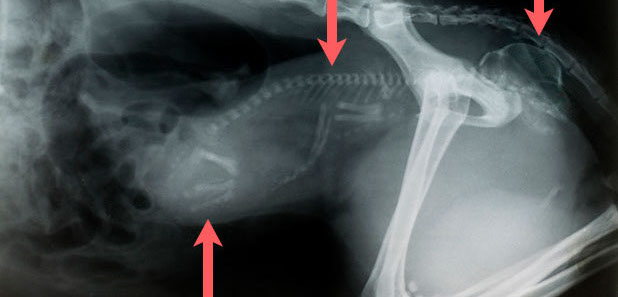

Zwei Diabologeschosse im Körper einer Katze

Mehrfachfrakturen nach Autounfall mit Lähmung der Hinterextremitäten, Hund